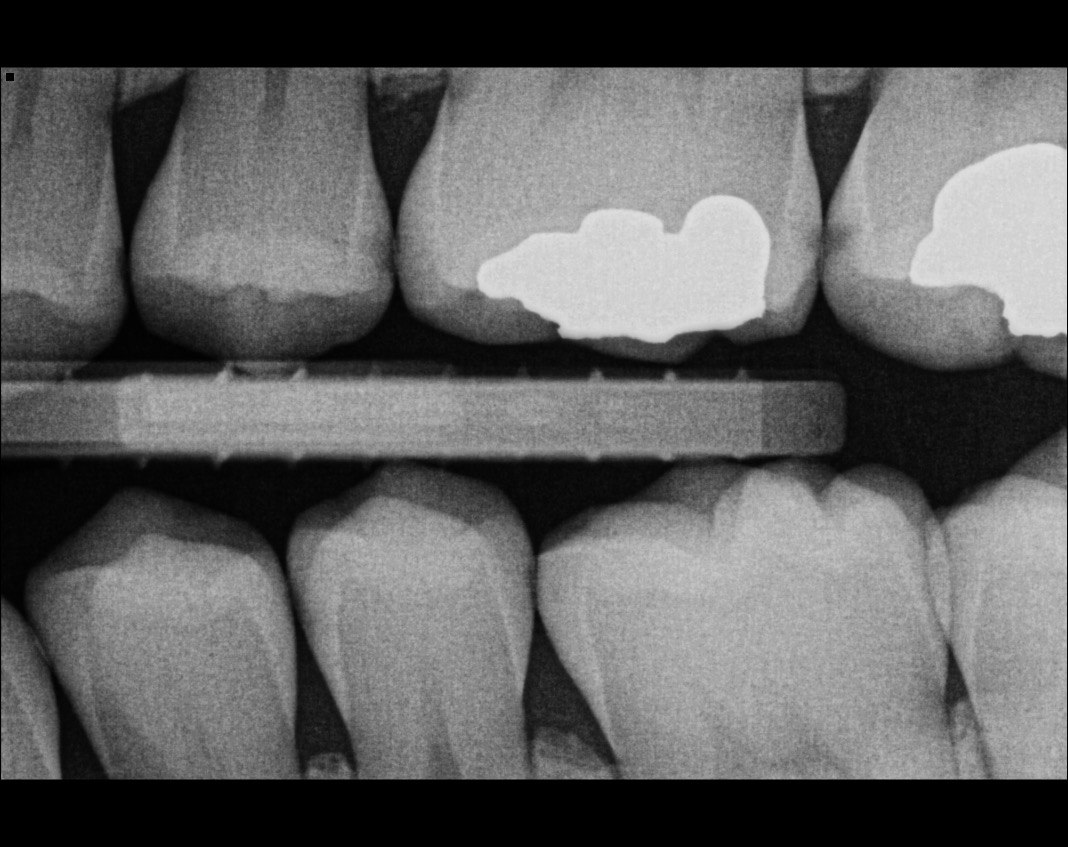

Question 5: Which surface shows recurrent caries?

Question 6: Which surface shows recurrent caries?